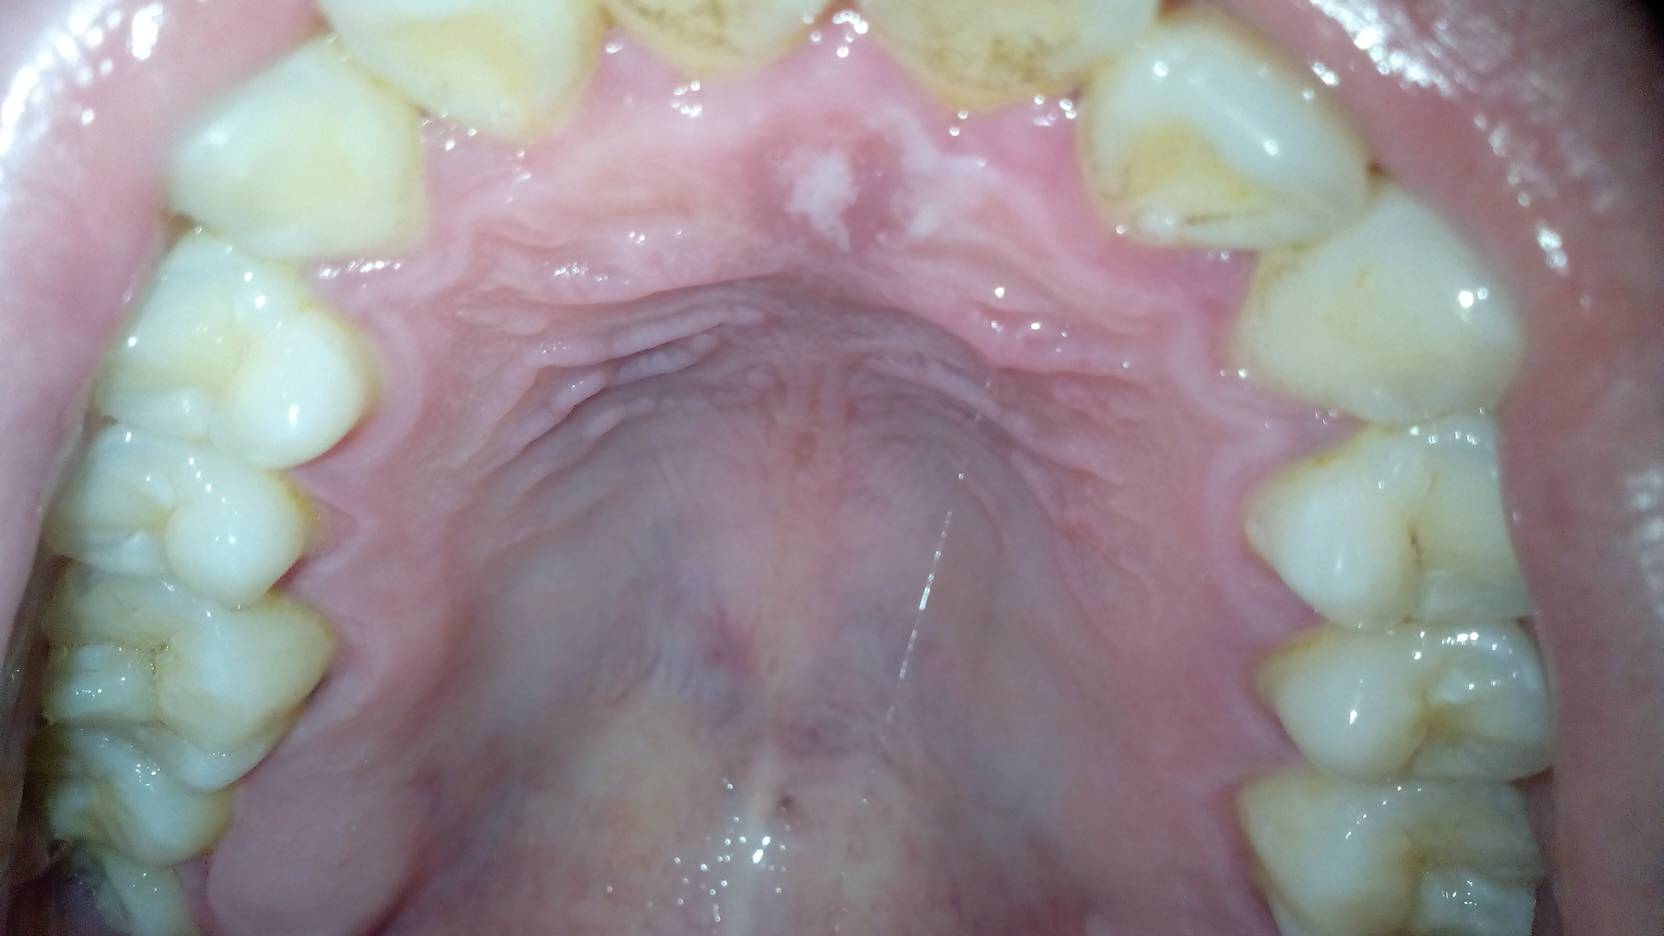

口腔粘膜白斑图片62

口腔白斑

口腔白斑病

口腔粘膜白色大斑块